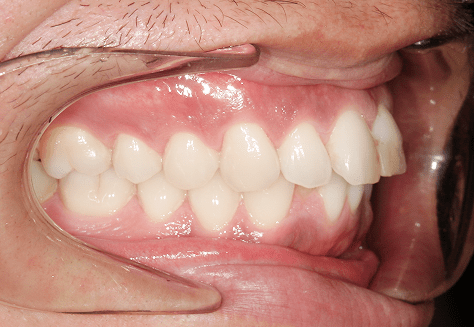

M.M

治療前

治療後

主訴

嚙み合わせが悪い。八重歯が気になる。

診断

叢生・反対咬合

年齢/性別

10代/女性

抜歯部位

非抜歯

使用装置

インビザラインファースト→インビザラインフェーズⅡ(部分的にワイヤーにて処置)

保定装置

上下ビベラリテーナー

料金

初回資料採得・・・・・・・30,000円

診断料・・・・・・・・・・0円

動的治療終了時資料採得・・5,500円 -

基本料金

円ファースト時:450,000円

フェーズⅡ時:240,000円 -

診察料金

ファースト時:0円×16回

フェーズⅡ時:5,500円×9回

ワイヤー併用時:8,800円×2回 -

治療期間

2年7カ月